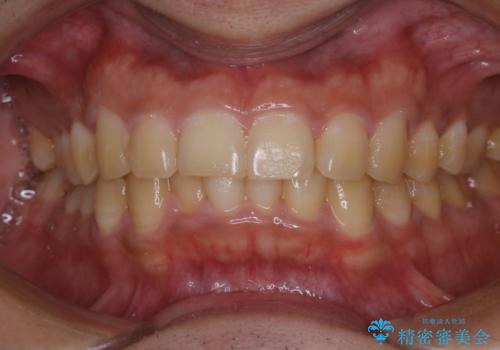

数年ぶりに歯のクリーニング(PMTC)

- しばらく歯科へ行っていなかったため綺麗にクリーニングしたいとのことでした。全体的に汚れが付着していたためPMTC60分コースを行いました。